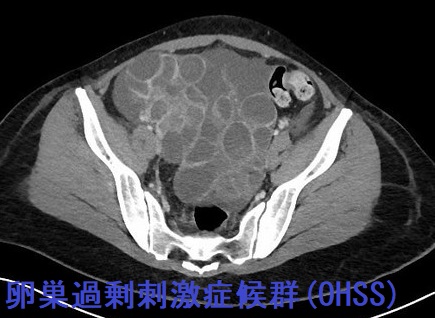

不妊治療で卵胞成熟ホルモン(FSH)製剤・ヒト閉経後ゴナドトロピン(hMG)製剤、ヒト絨毛性性腺刺激ホルモン(hCG)製剤を投与して卵巣を刺激し過ぎると、卵巣腫大・卵巣茎捻転、血管内皮増殖因子(VEGF)過剰産生による腹水・胸水貯留等を引き起こす(卵巣過剰刺激症候群:OHSS)。黄体化過剰反応は妊娠・絨毛性疾患(全胞状奇胎・絨毛性腫瘍)による高hCG状態で生じる両側卵巣腫大。甲状腺機能低下症で甲状腺ホルモン剤を服薬中の女性で胚移植の際、卵巣過剰刺激症候群(OHSS)と急激な甲状腺機能低下症増悪を同時に来した報告がある。

- 画像;両側卵巣腫大と多量の腹水貯留

卵巣過剰刺激症候群(OHSS)を起こした状態で妊娠すると、血栓症・急性腎不全・急性循環不全によるショックで死亡する危険があります。卵巣過剰刺激症候群(OHSS) のリスクが高い場合、受精卵はすべて凍結保存し、落ち着いてから胚移植します。